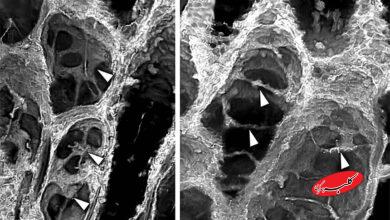

در منابع علمی، این وضعیت تحت عنوان «Dysphonia in Parkinson’s disease» یا اختلال صوتی در پارکینسون شناخته میشود و علت آن، تغییرات ساختاری و عملکردی در عضلات حنجره و تارهای صوتی است. با پیشرفت بیماری، عضلات تارهای صوتی ضعیف و نازک میشوند، ارتعاش طبیعی آنها مختل میشود و در نتیجه، صدای فرد تغییر میکند.

همچنین، پژوهشهایی در زمینه تزریق ژل به تارهای صوتی برای بهبود ارتعاش و بسته شدن آنها انجام شده است. در یکی از مطالعات دانشگاه کلرادو، تزریق ژل باعث بهبود ۱۶ درصد در بسته شدن تارهای صوتی و افزایش وضوح صدا در بیماران پارکینسون شد.

جالب است بدانید که برخی پژوهشگران معتقدند تغییرات صوتی میتوانند یکی از اولین نشانههای بیماری پارکینسون باشند. در دانشگاه موناش استرالیا، پژوهشی در حال انجام است که با استفاده از سیتیاسکن، تغییرات صوتی را بهعنوان ابزار تشخیص زودهنگام بررسی میکند. هدف این است که بتوان بیماری را تا ۸ سال زودتر از روشهای فعلی تشخیص داد.